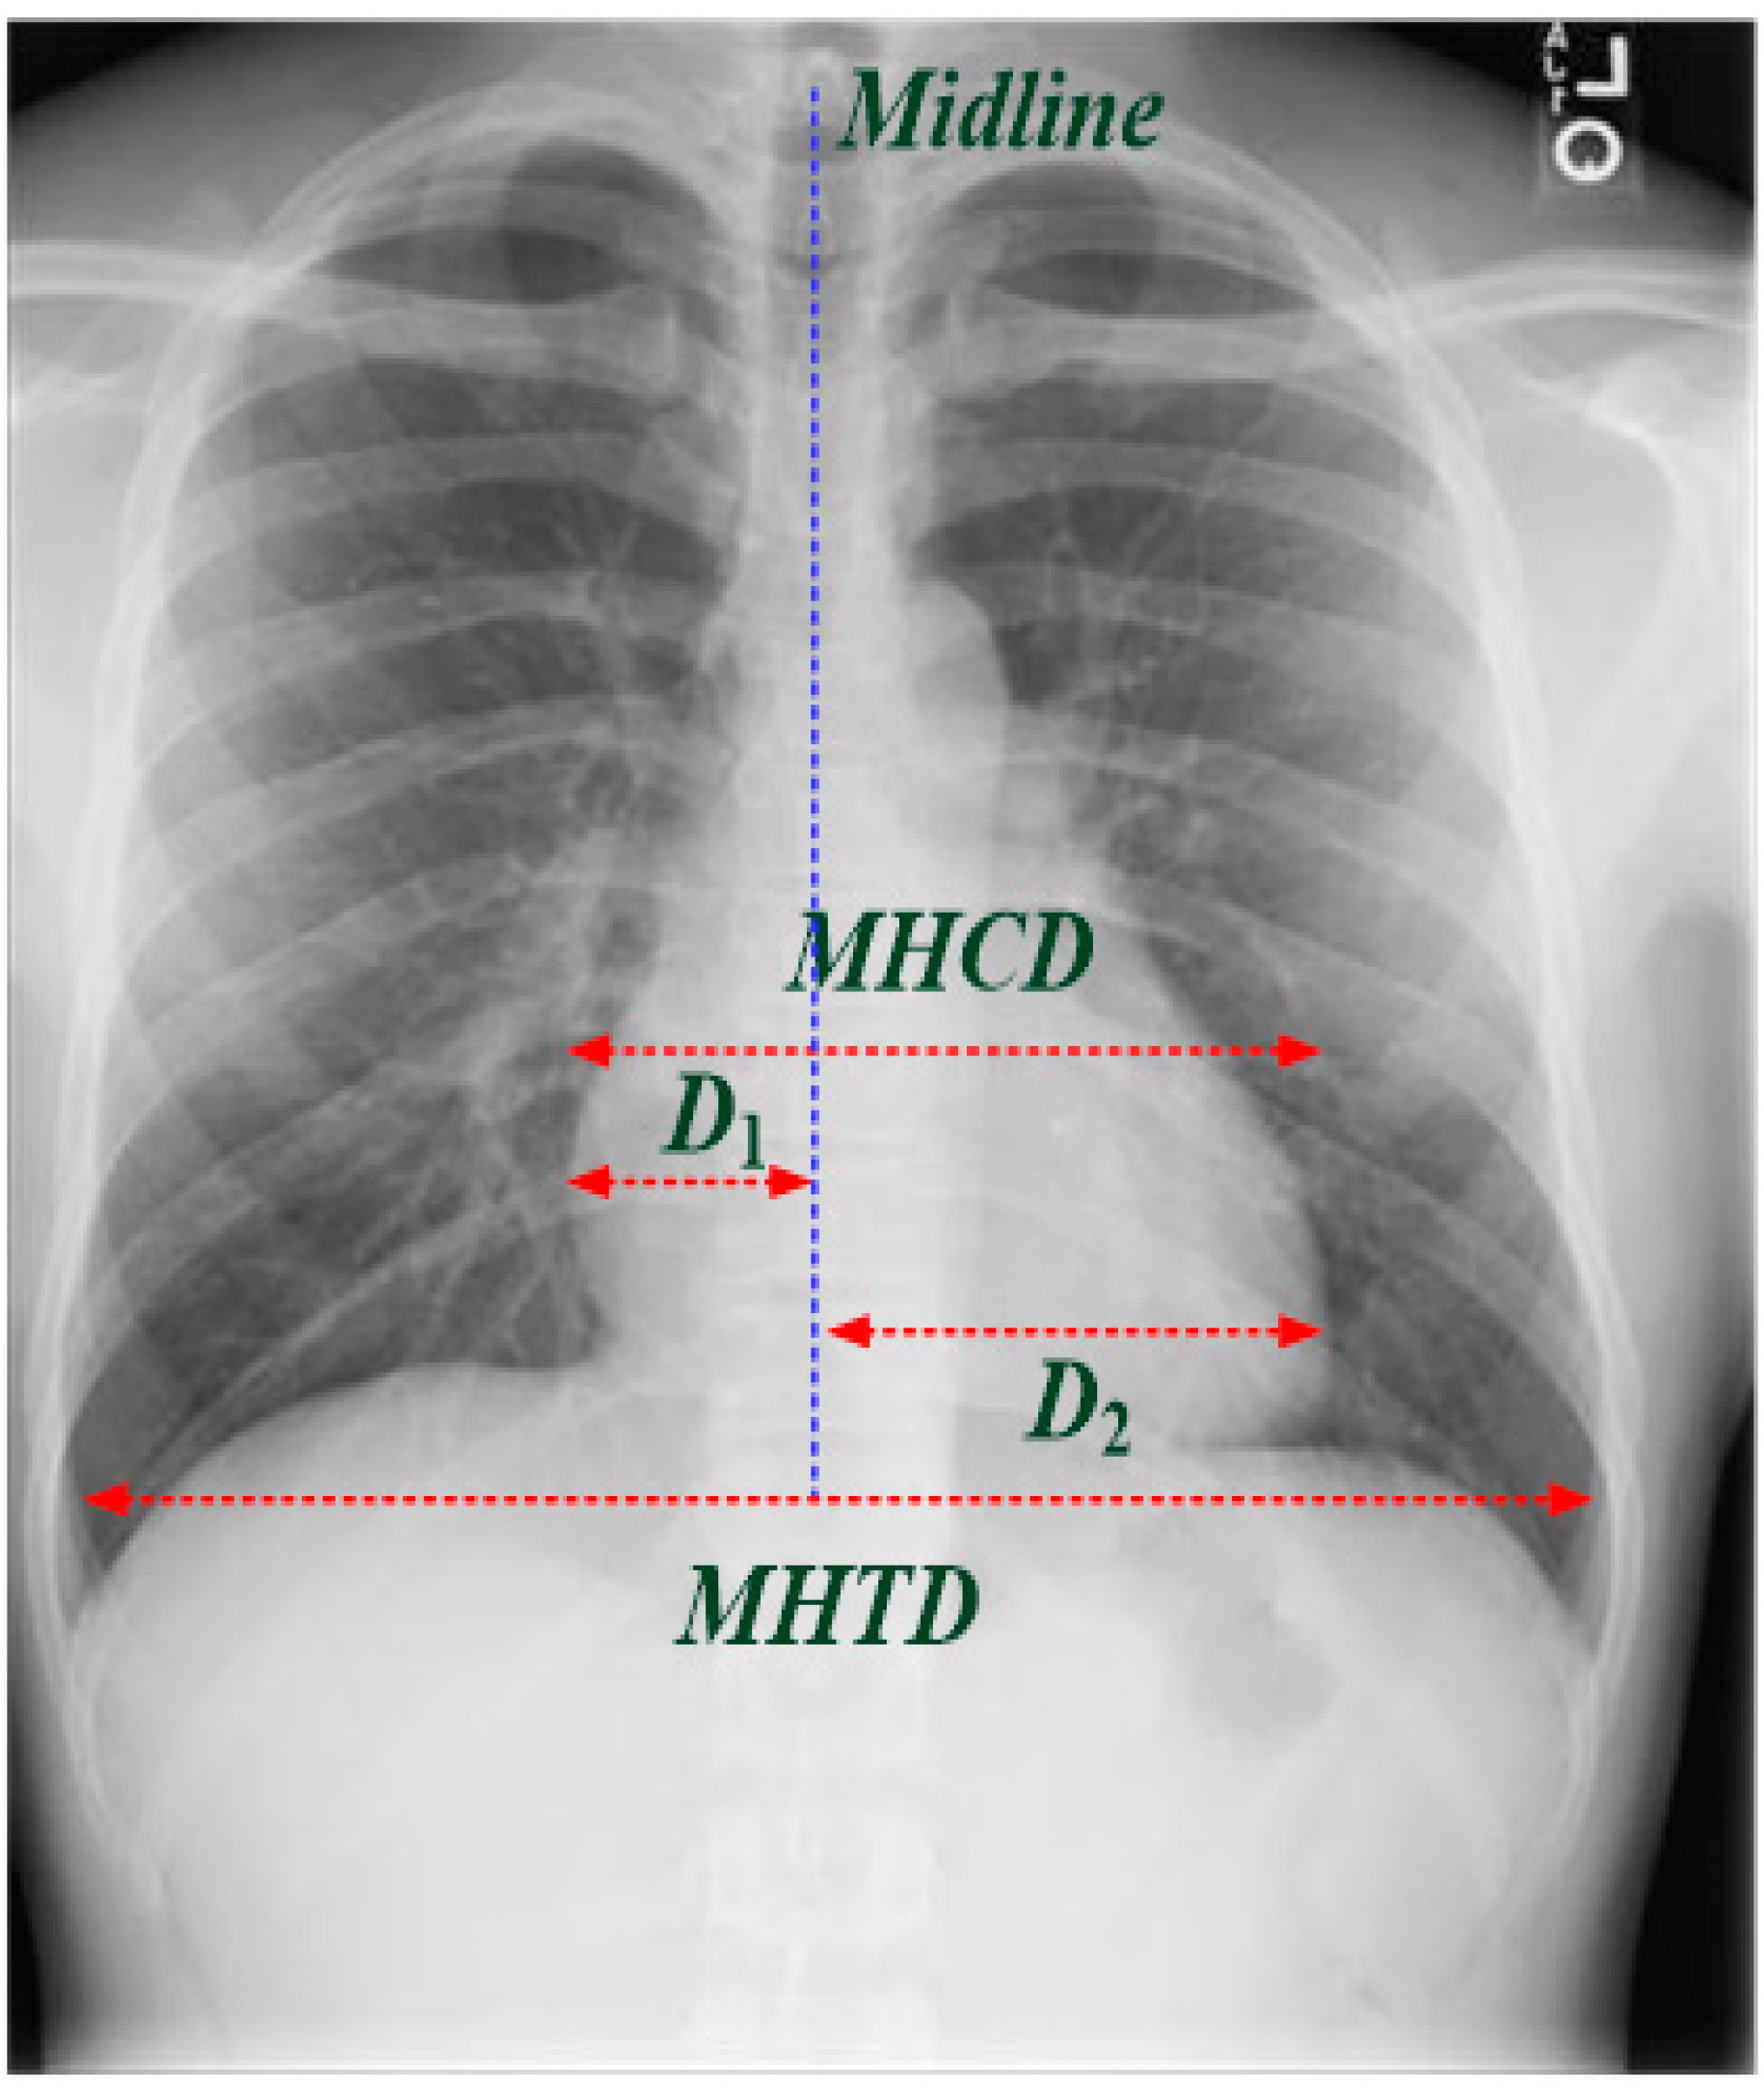

How To Detect Cardiomegaly On Chest X Ray . To determine whether or not cardiomegaly identified on chest radiograph (cxr) is indicative of true cardiomegaly as. there are generally three methods for assessing the size of the heart on a plain chest radiograph. Find out how radiologists diagnose and. deep learning using transfer learning methods based on vgg19 network can be used for the automatic detection of cardiomegaly on.

To determine whether or not cardiomegaly identified on chest radiograph (cxr) is indicative of true cardiomegaly as. deep learning using transfer learning methods based on vgg19 network can be used for the automatic detection of cardiomegaly on. there are generally three methods for assessing the size of the heart on a plain chest radiograph. Find out how radiologists diagnose and.